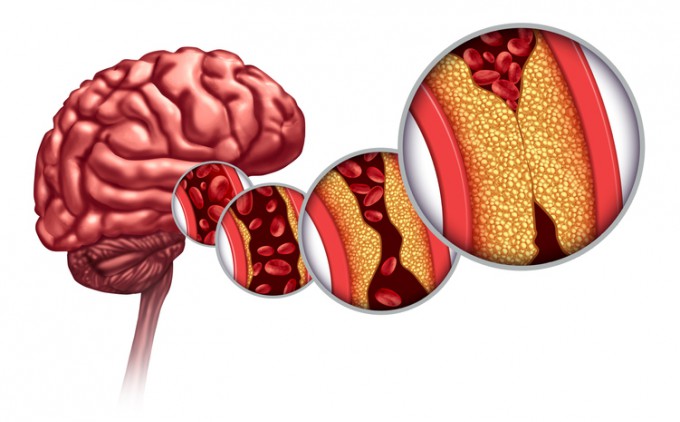

- 염분 섭취를 줄이고 과일, 채소, 통곡물 등 균형 잡힌 식단을 유지하세요. 혈압과 콜레스테롤 수치를 관리하는 데 도움이 됩니다.

- 흡연은 혈관을 수축시키고 혈전을 유발할 수 있으므로, 금연이 뇌졸중 예방에 중요합니다.

- 과도한 음주는 혈압을 높이고 뇌졸중 위험을 증가시키므로, 절주를 생활화하세요.

- 정기적인 혈압과 콜레스테롤 검사